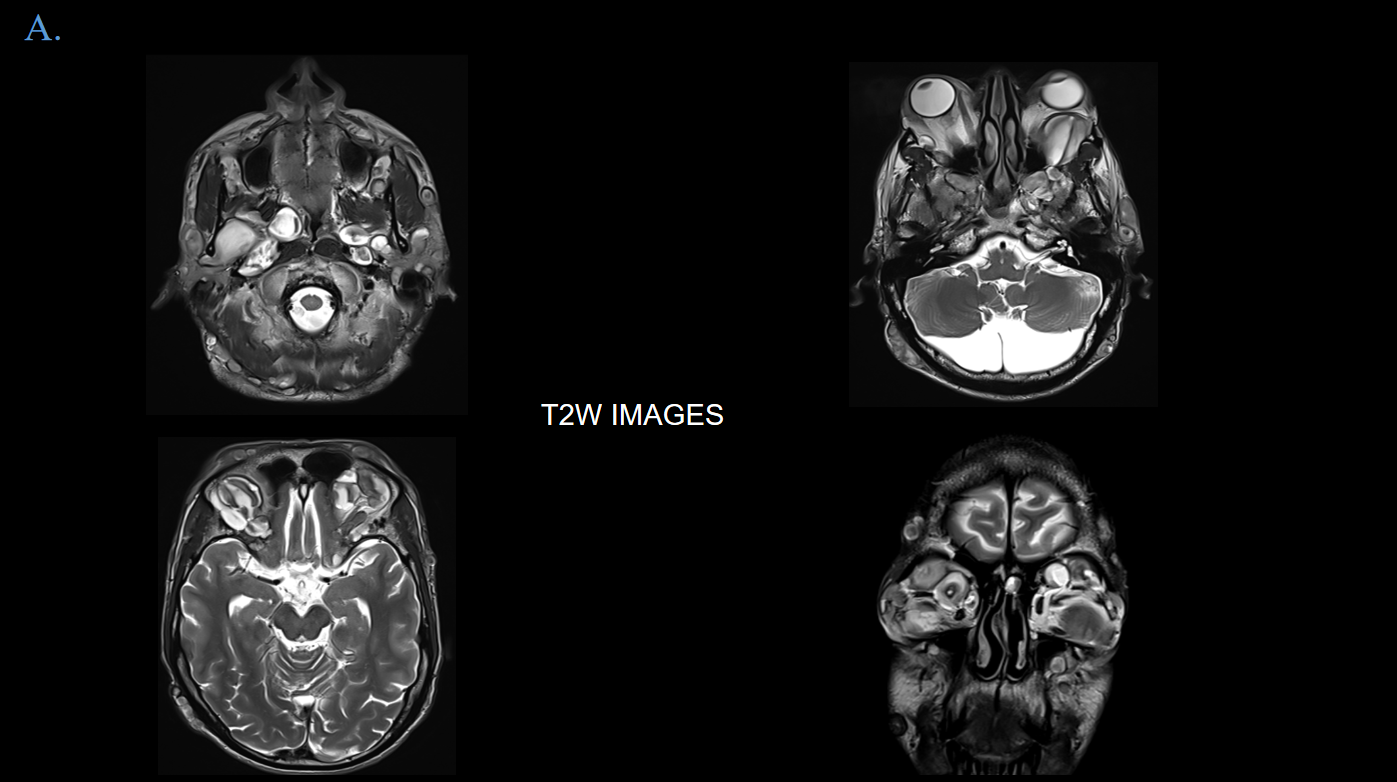

View Case45 year old female presents with complaints of headache, giddiness and occasional vertigo for which MRI Brain was advised.

45 year old female presents with complaints of headache, giddiness and occasional vertigo for which MRI Brain was advised.